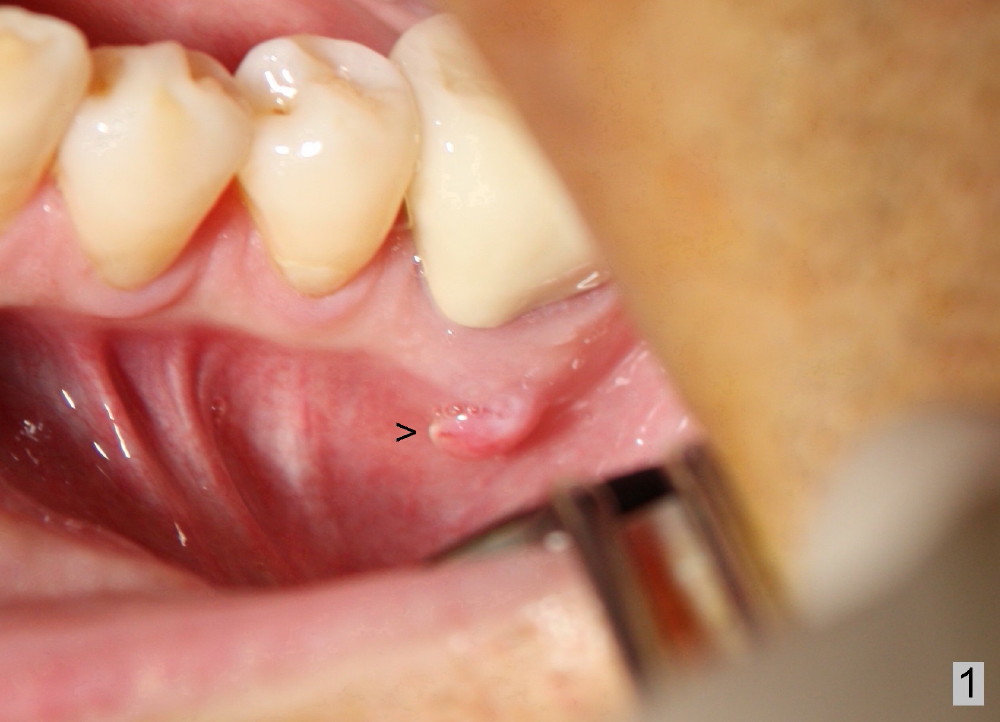

A 41-year-old man has discomfort in the lower left 1st molar. Exam shows swelling and a fistula in the mesiobuccal gingiva (Fig.1 >) and large radiolucency around the mesial root (Fig.2 *). After extraction and thorough debridement, osteotomy is initiated in the mesial socket, but the upper portion of the reamer (Fig.3 R, 2.5 mm) is placed in the middle of the edentulous space. By the time 5 mm reamer is removed, the osteotomy (Fig.4 O) forms mainly in the mesial socket with the septum (S) deviated to the distal socket. A 7x17 mm tap is placed with stability (Fig.5 T). An implant with the same dimension is placed with insertion torque more than 60 Ncm (Fig.6 I). With the large implant, two proximal sutures are able to close the remaining socket gaps (Fig.7). The swelling and fistula disappears and the gingiva tightly surrounds the implant in 1 week postop (Fig.8).